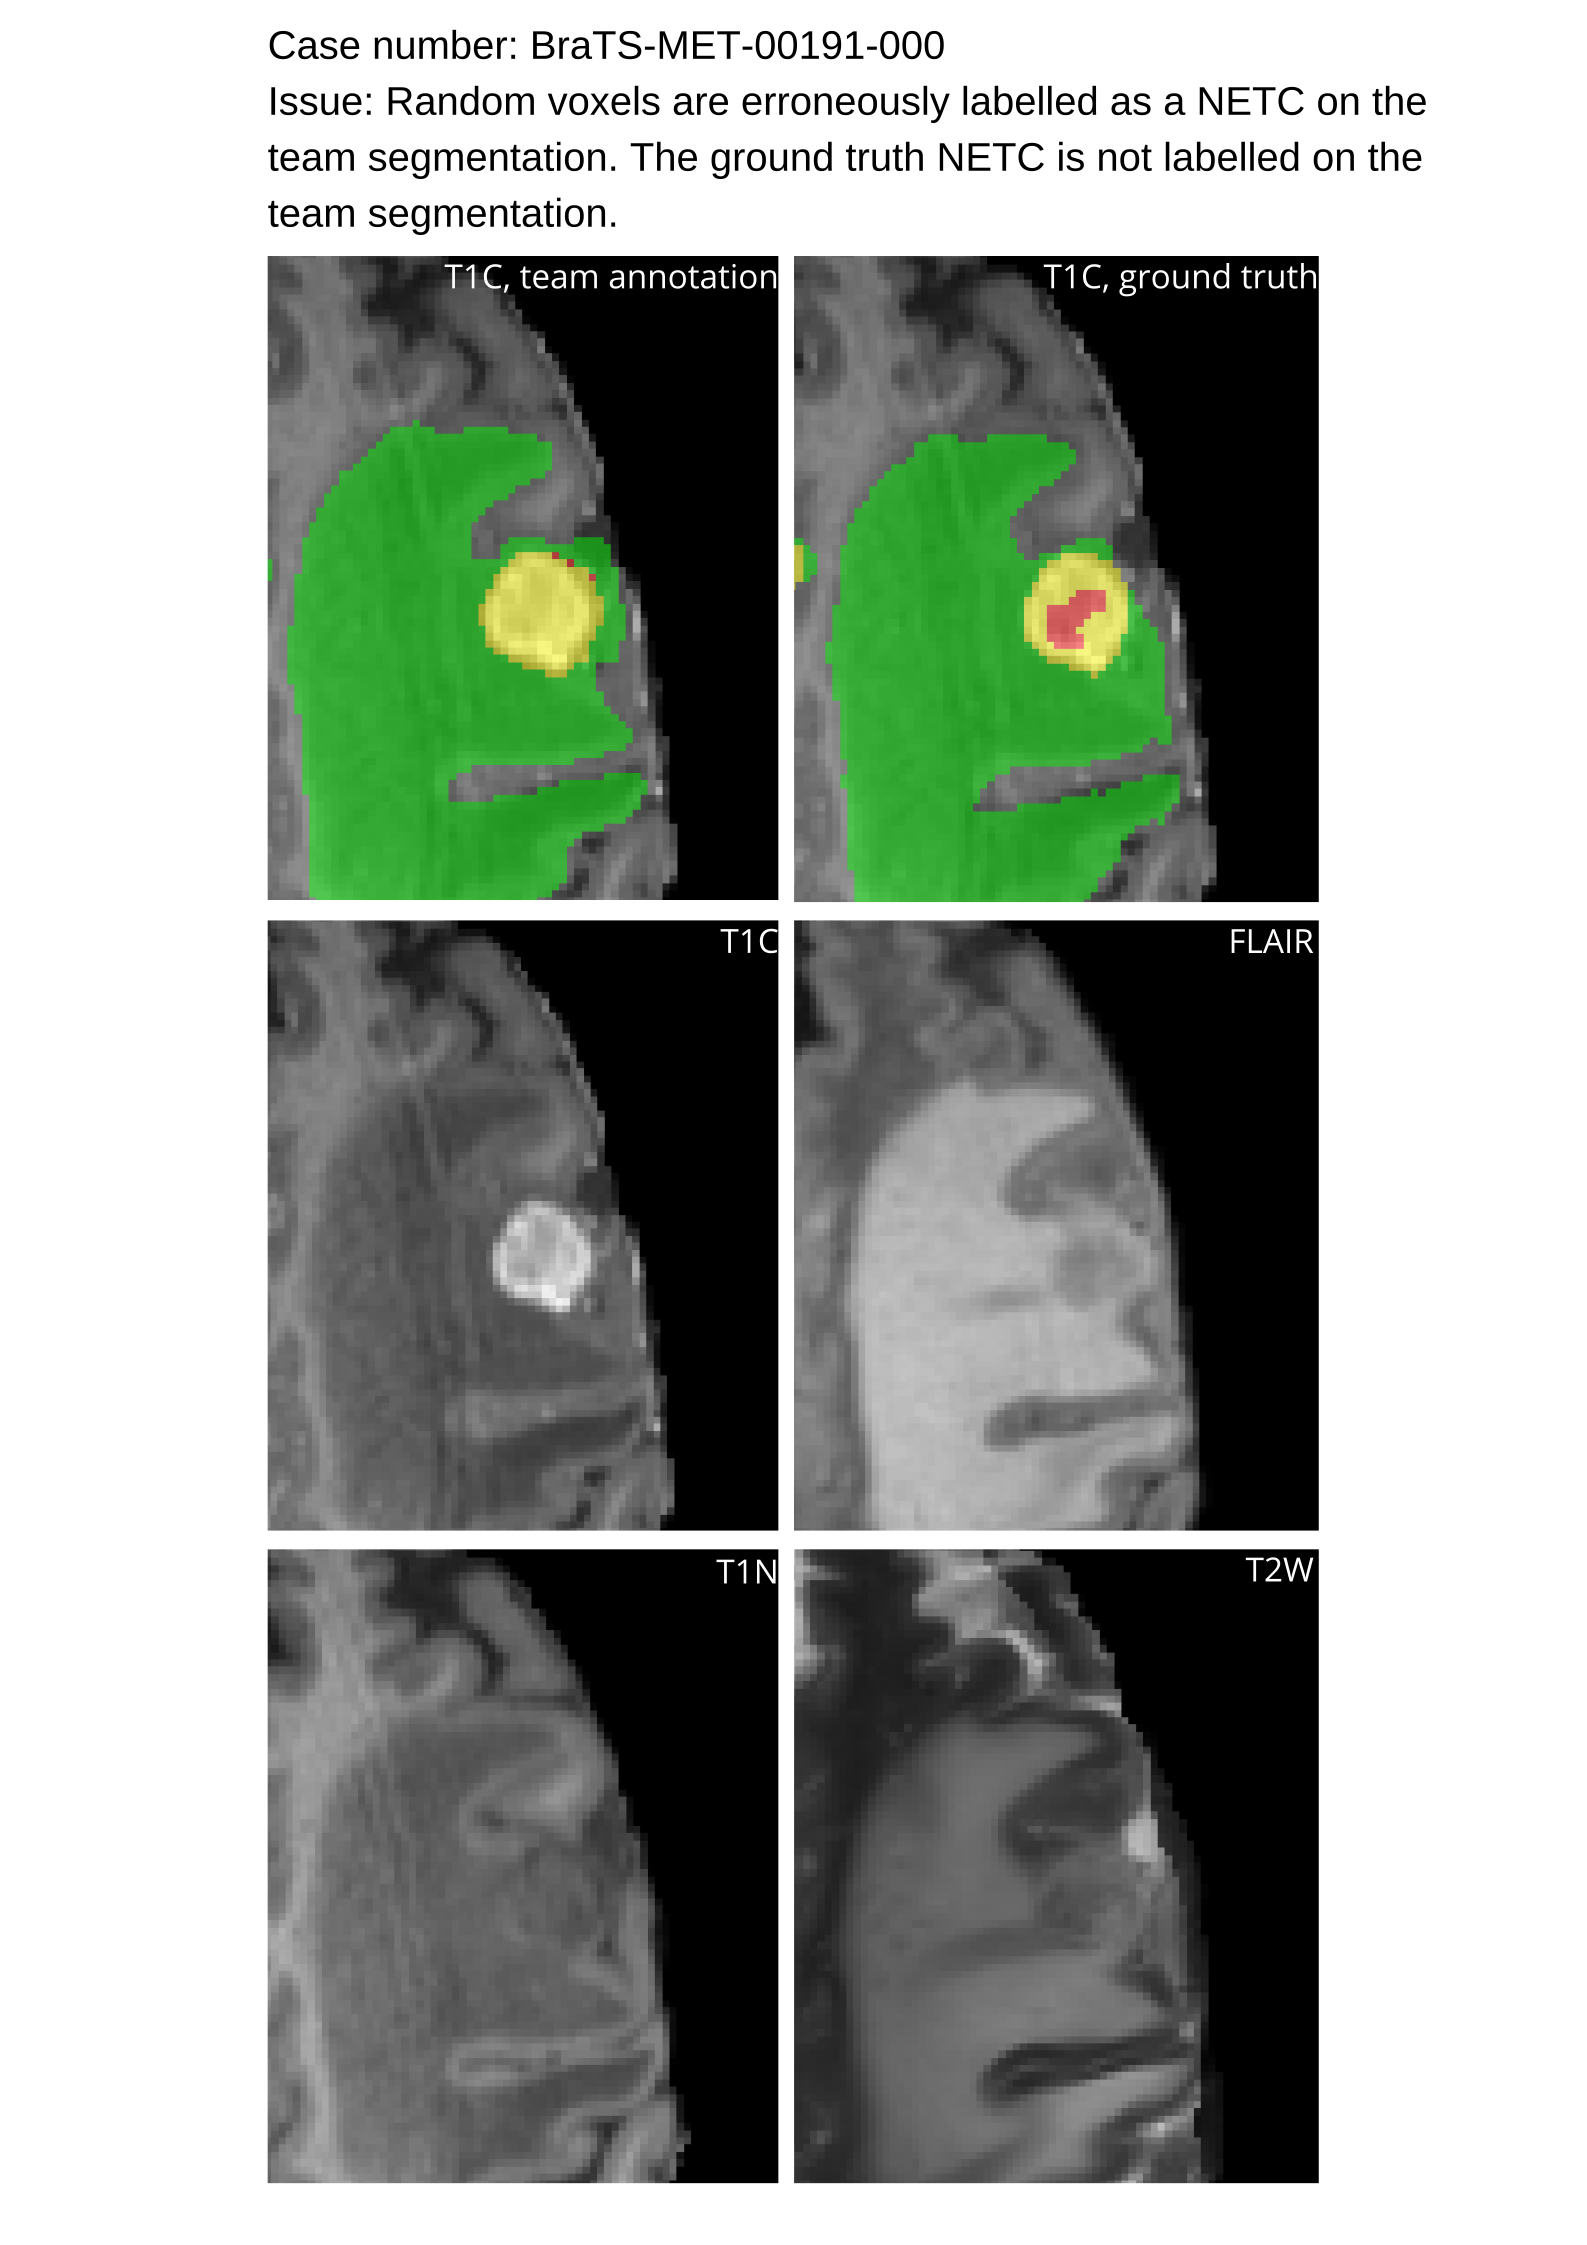

Approvers reviewed the volunteer annotations and either approved the case or returned it to students for re-annotation. Additionally, a QC process was implemented, which included removing all random voxels and any voxels outside the brain mask, ensuring all images had the same parameters (space, orientation, and origin) as the SRI24 atlas, and verifying the presence of all segmentations and segmentation masks are in the folder with original NIfTI images.